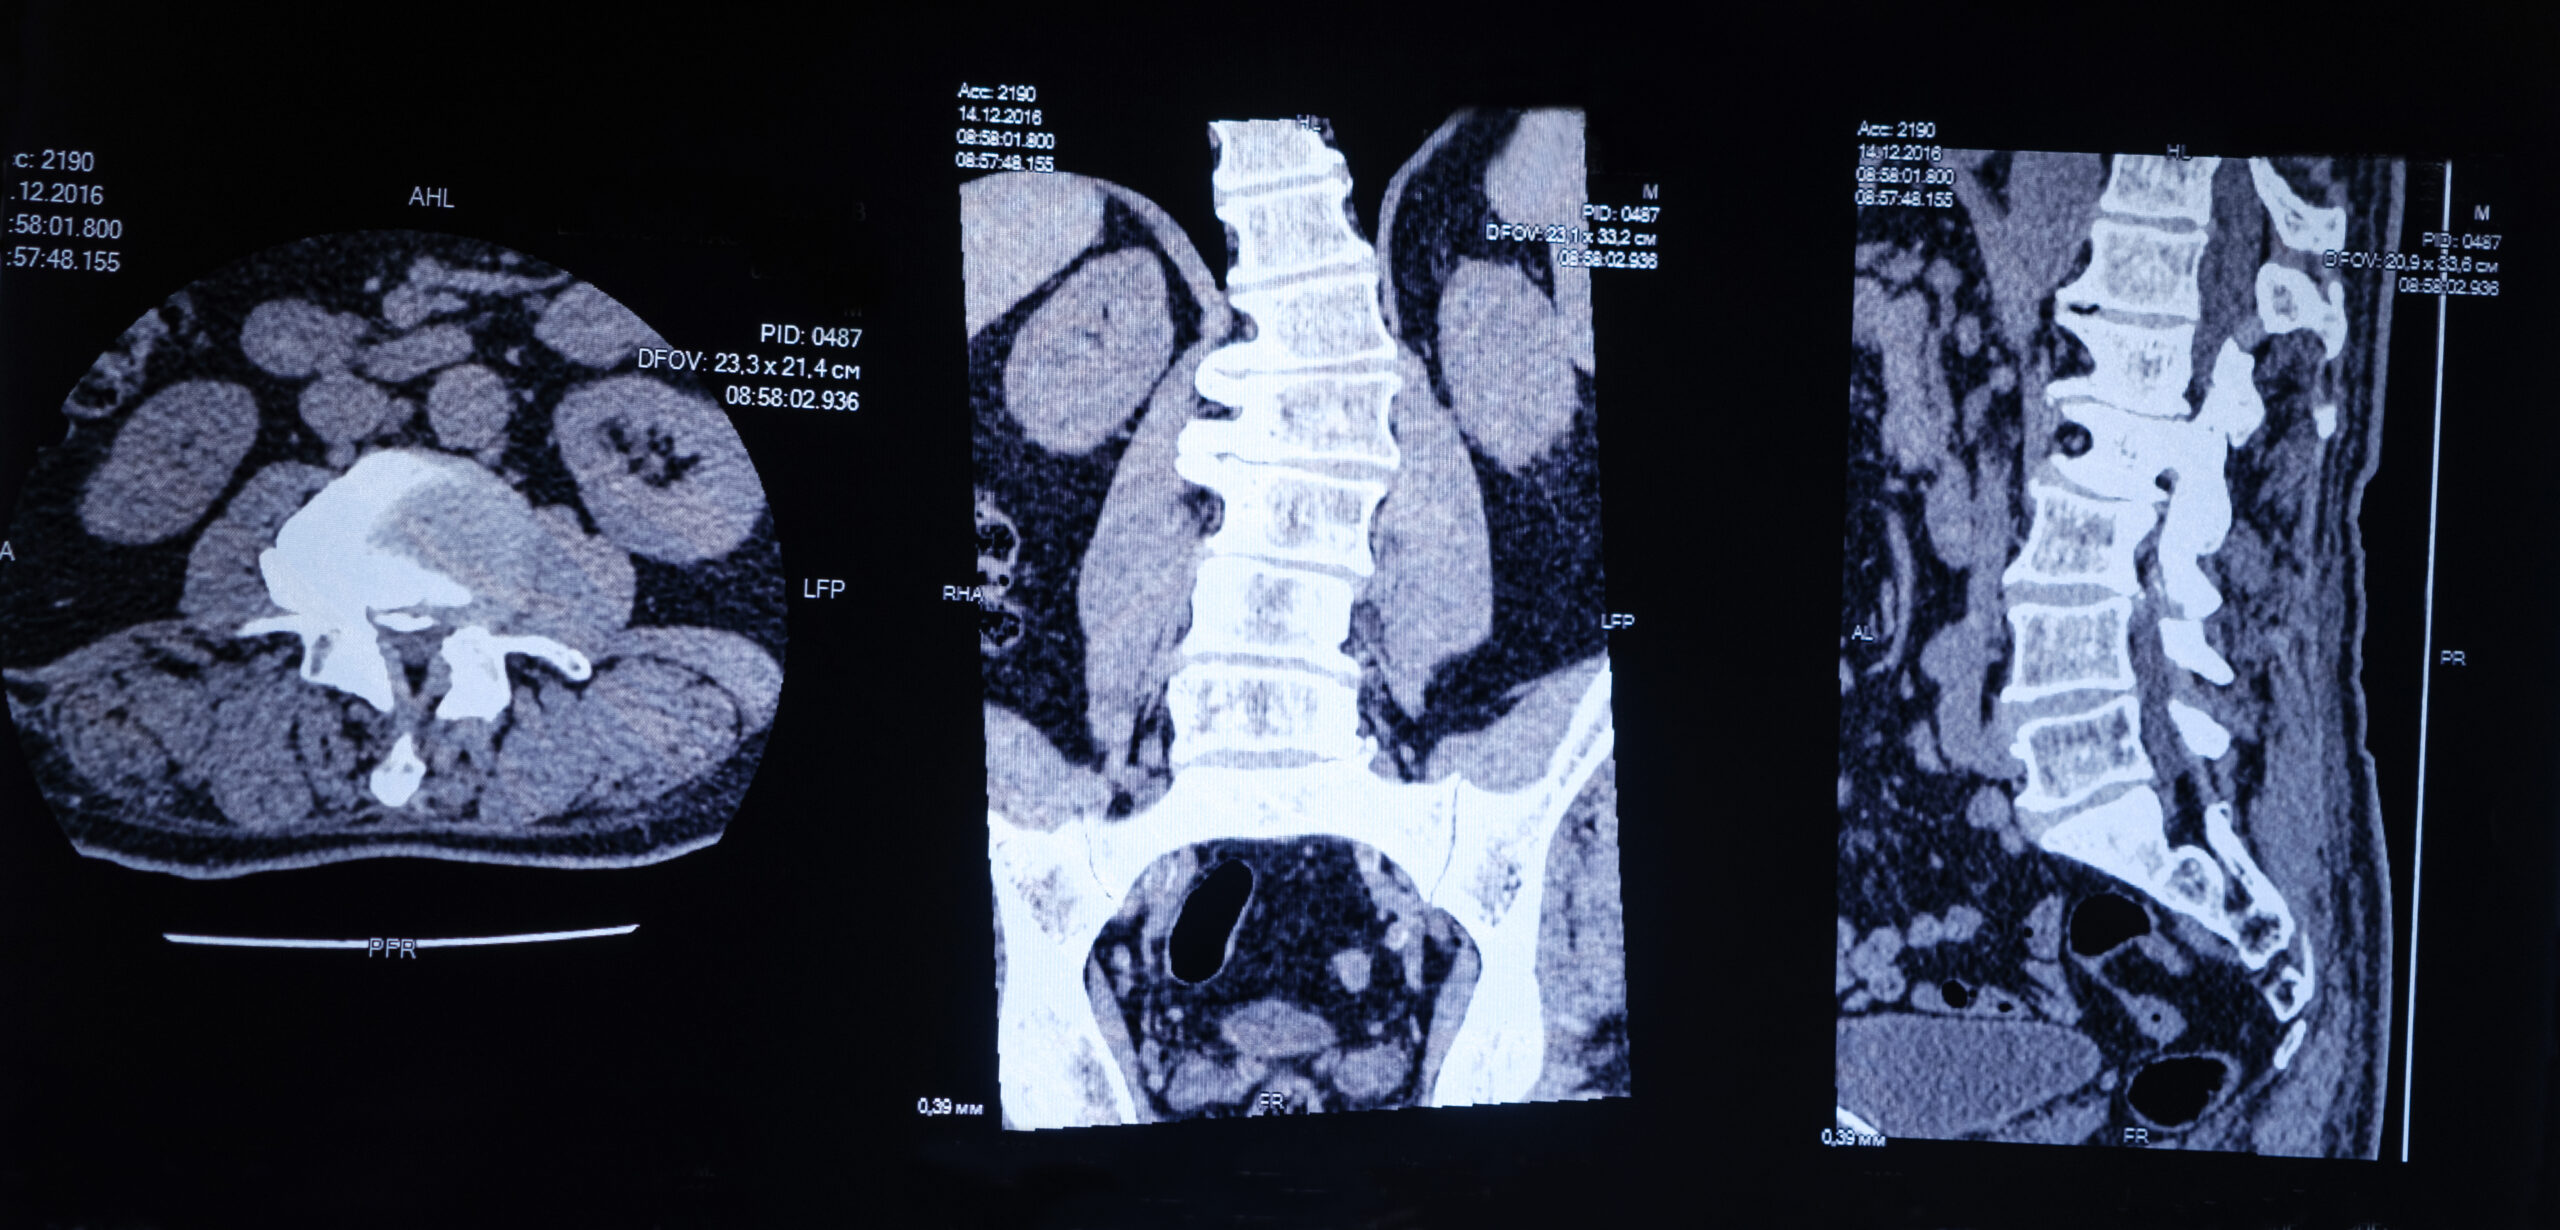

Spinal disorders such as degenerative disc disease, herniated discs, and spondylolisthesis are increasingly common due to modern lifestyles, aging, and spinal injuries. As the demand for advanced spinal solutions grows, so does the innovation in surgical techniques. One such revolutionary approach is the Minimally Invasive Trans Kambin Fusion Surgery, known as OLLIF (Oblique Lateral Lumbar Interbody Fusion) and KLIF (Kambin’s Triangle Lumbar Interbody Fusion).

OLLIF and KLIF are minimally invasive spinal fusion procedures performed through a natural opening in the spine called Kambin’s Triangle — a safe anatomical corridor located on the posterolateral side of the spinal disc. This pathway allows surgeons to access the disc space without cutting through muscles or moving nerve roots.

How Does the Procedure Work?

The OLLIF/KLIF technique involves the following steps:

- Positioning: The patient is placed on their stomach under general anesthesia.

- Access via Kambin’s Triangle: A small incision (less than 1 cm) is made, and the surgeon navigates to the disc space using real-time imaging (fluoroscopy).

- Discectomy and Fusion: The damaged disc is removed and replaced with a cage filled with bone graft material to encourage vertebral fusion.

- Stabilization: Percutaneous pedicle screws may be used for added support depending on the case.

This approach avoids significant muscle damage, leading to reduced postoperative discomfort and faster healing.